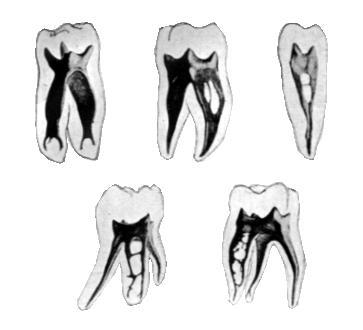

![]() |

Az alsó nagyőrlő fogon jól látszanak a gyökércsatornák bemeneti nyílásai a gyökértömés előtt... |